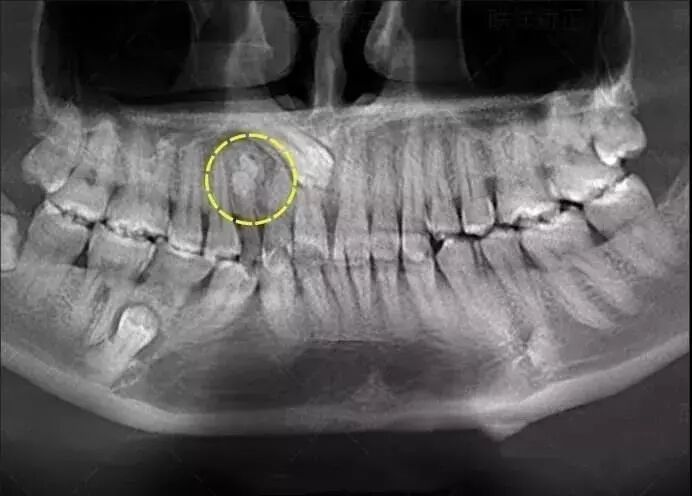

但係用啲牙片都可以揾到問題,你會發現,除咗龍鳳呀,你的口腔内还有肉眼无法确认的其它牙科问题,

例如“藏住喇”的多生牙,唔影牙片咁任住佢,定係你唔介意啊,導致更嚴重嘅後果!